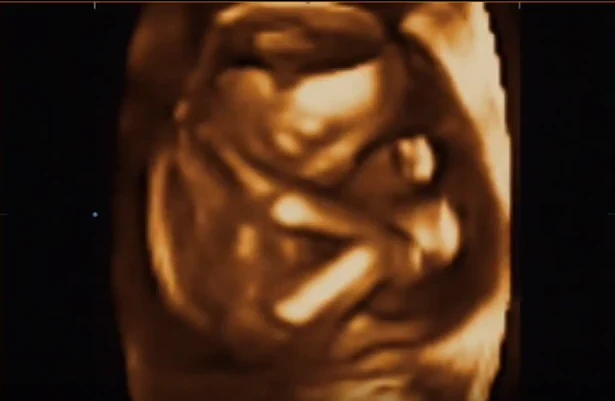

Tanulva a múltkori alkalomból, benyomtam egy szelet csokit az ultrahang előtt 15 perccel, hogy a kicsi mozgolódjon, ne alukáljon. Az ultrahangos orvos ránk mosolygott és mondta, hogy ő már tudja a nemét, de majd mindjárt megmutatja nekünk. Pár perc múlva megláttuk az ultrahangon azt a kis testrészt, ami egyértelműen arról tanúskodik, hogy kisfiúnk lesz. Fantasztikus érzés volt, de akkor még fel sem fogtam igazán, csak később a kocsiban, ahogy hallgattam páromat, aki lelkesen mesélte a leendő nagypapáknak és nagymamáknak, nagynéniknek és a haverjainknak, hogy képzeljék, nekünk bizony fiúnk lesz.